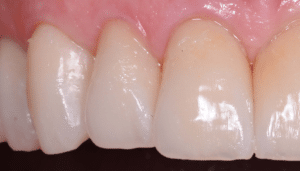

Fig 9

Réponse parodontale à seulement 8 jours post opératoire. L’élimination de tout le ciment en excès à permis une rapide cicatrisation parodontale.